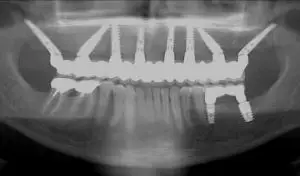

На рисунке ниже можно увидеть дополнительный рентгеновский снимок стоматологического решения по принципу All on 8,

которое выполняется таким же способом и на основе одних и тех же руководящих принципов: